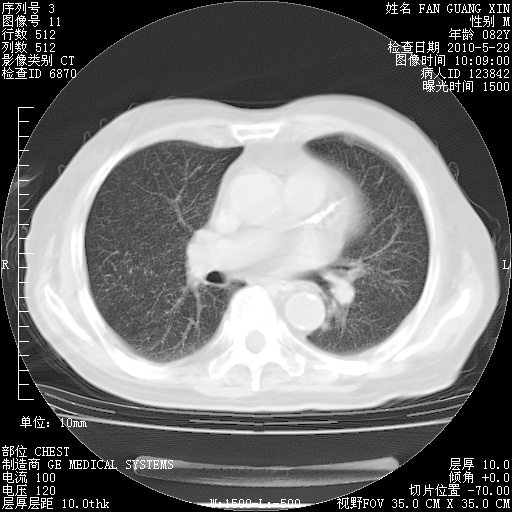

再治疗10天后的肺部CT

再治疗10天后的肺部CT 纵膈窗